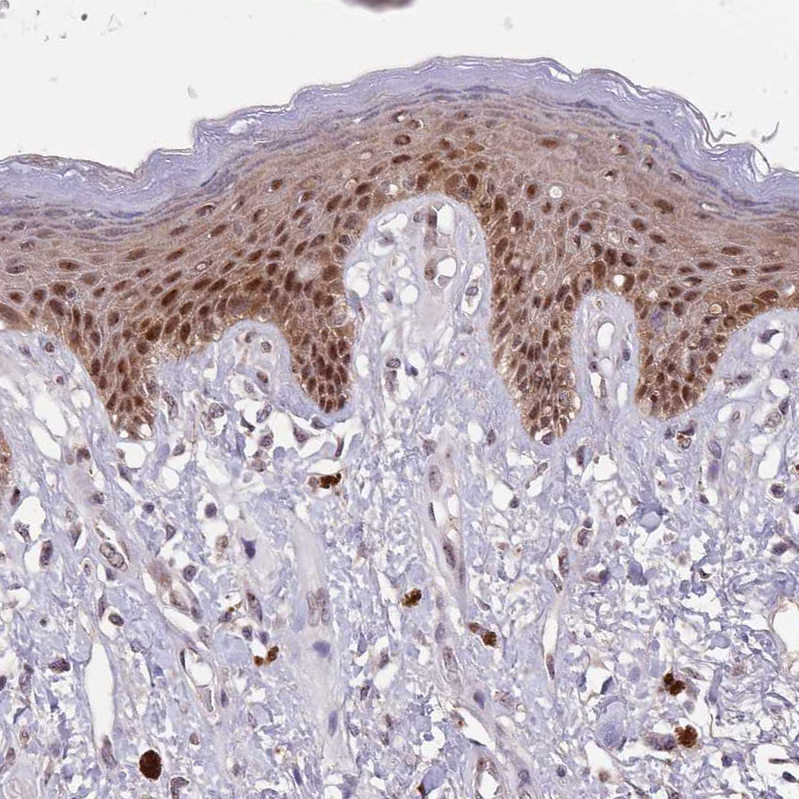

Immunohistochemical staining of human skin shows strong nuclear positivity in squamous epithelial cells.